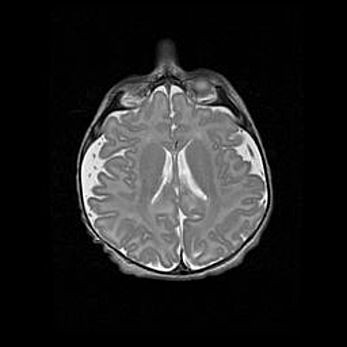

Открытая гидроцефалия.

Возраст: 6 месяцев 15 дней

Вес: 6200 г

Пол: женский

Окружность головы: 41 см

Срок гестации: 38 недель

Гидроцефалия головного мозга у новорожденных – это скопление избыточного количества цереброспинальной жидкости в головном мозге. Ее избыточное скопление в мозге приводит к патологическому расширению желудочков мозга (четырех полостей, расположенных в глубине белого вещества мозга, заполненных цереброспинальной жидкостью и связанных узкими проходами).

Открытый тип гидроцефалии (сообщающаяся) наблюдается тогда, когда нарушен механизм всасывания ликвора в системный кровоток. При этом типе причиной заболевания чаще всего является перенесенные ранее инфекции (например: менингит),  либо же наличие крови в субарахноидальном пространстве.